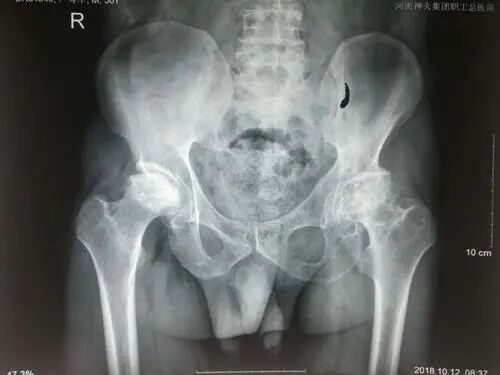

在正位X线片上,髋白发育不良主要表现为髋白发育浅小或浅平,股骨头的负重侧间隙增宽,并继发骨性关节炎。髋关节正位、蛙位X线片是了解与判断髋关节发育不良程度的最基础的影像学检查。

髋关节CT检查有利于分析髋臼形态、判断髋臼缺损及增生情况,可为术式选择、评估假体型号和安装位置等提供帮助。MRI检查有助于发现关节盂唇损伤、关节囊改变及骨内信号改变等。